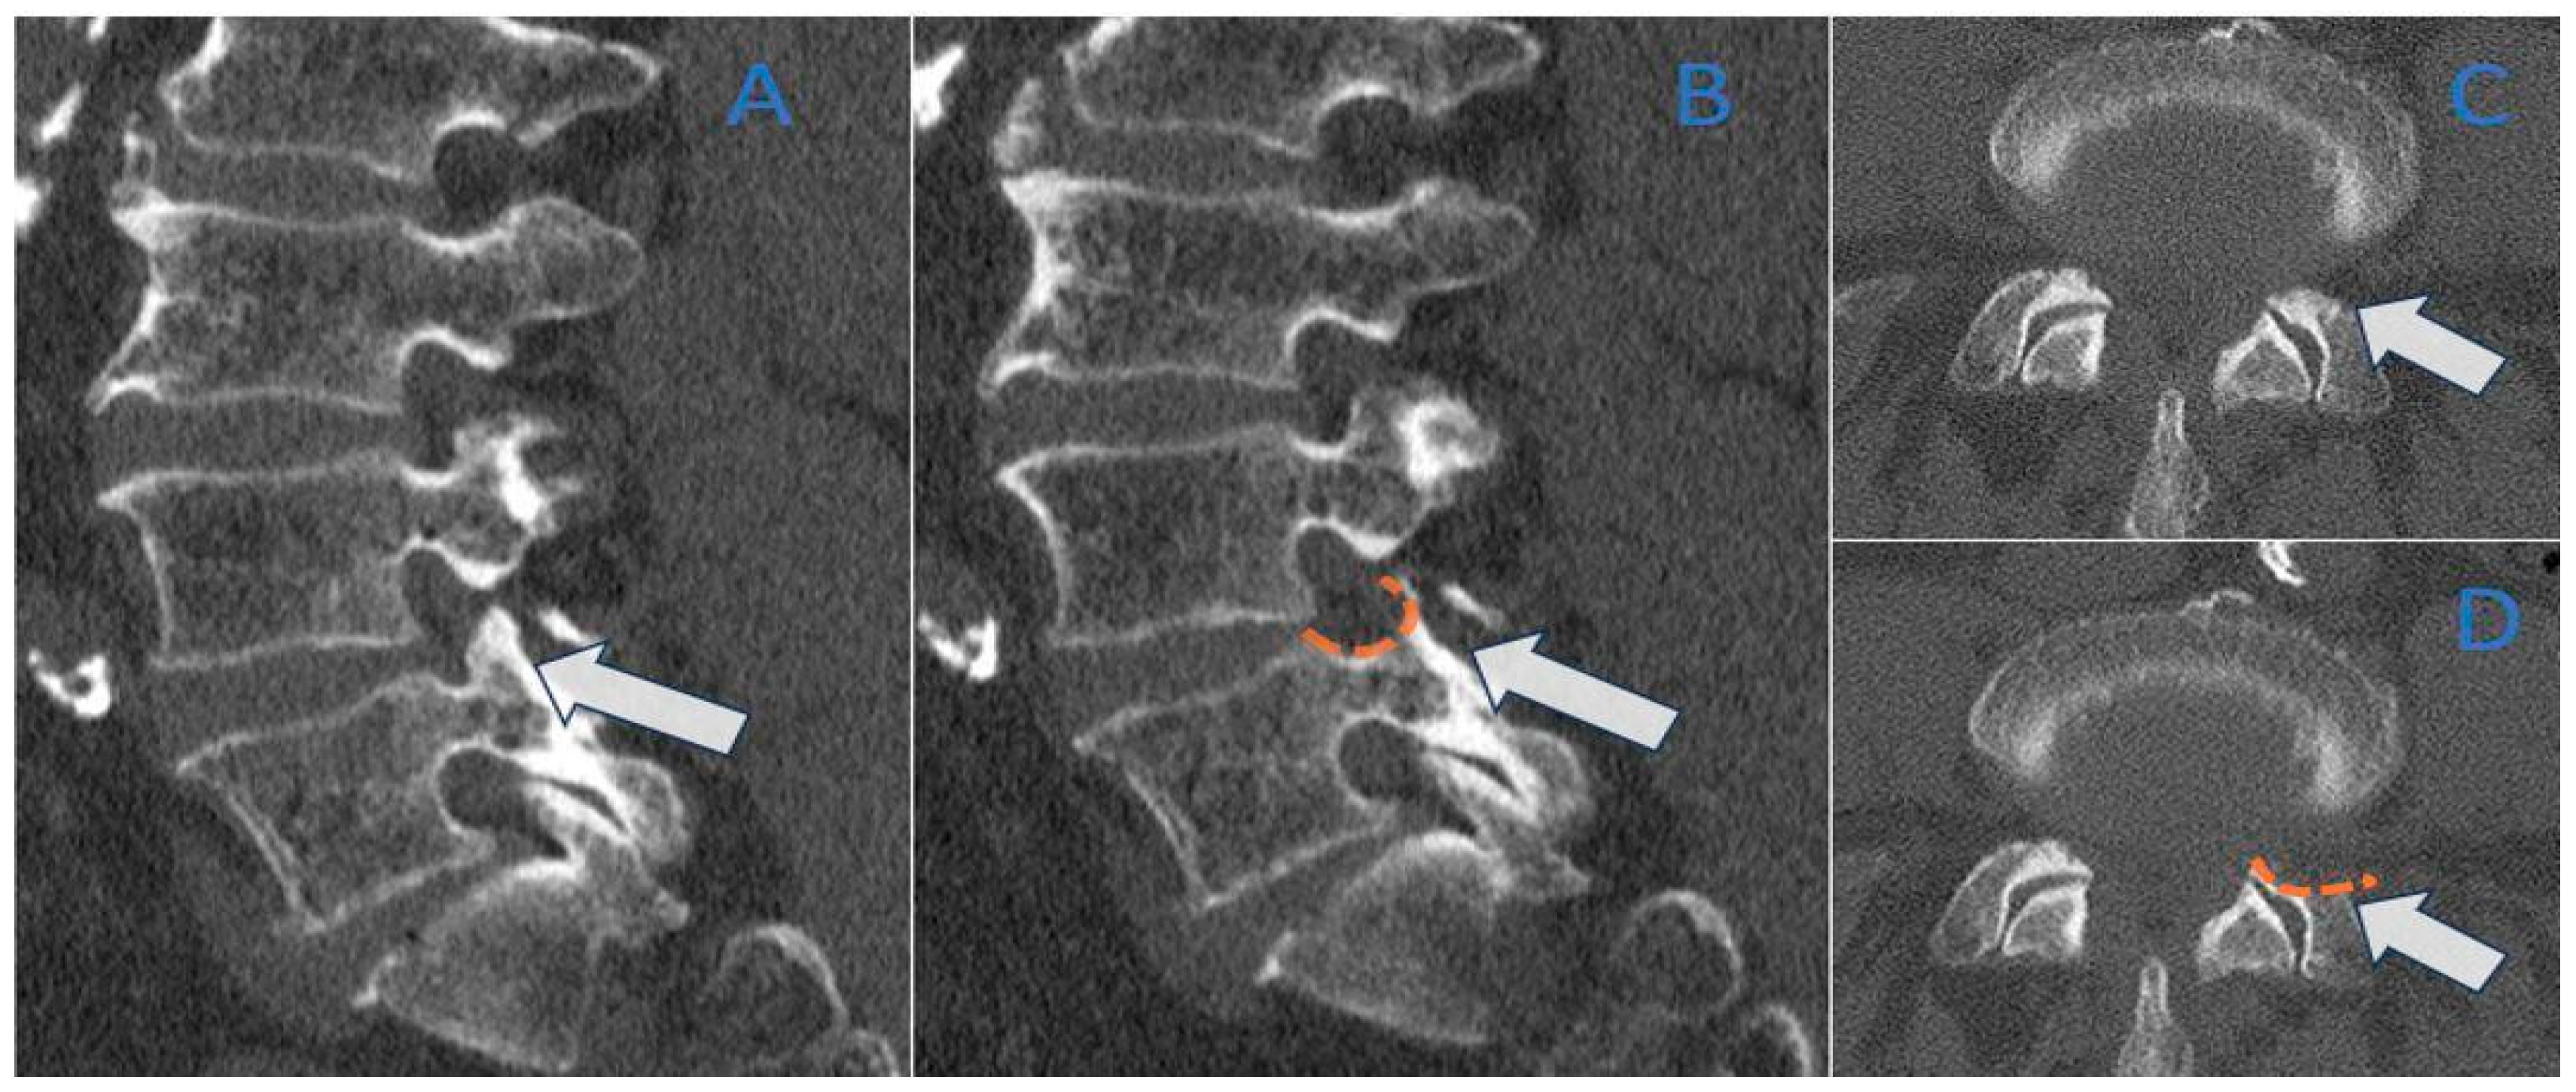

2.4. CT Post-Processing

2.5. Image Analysis